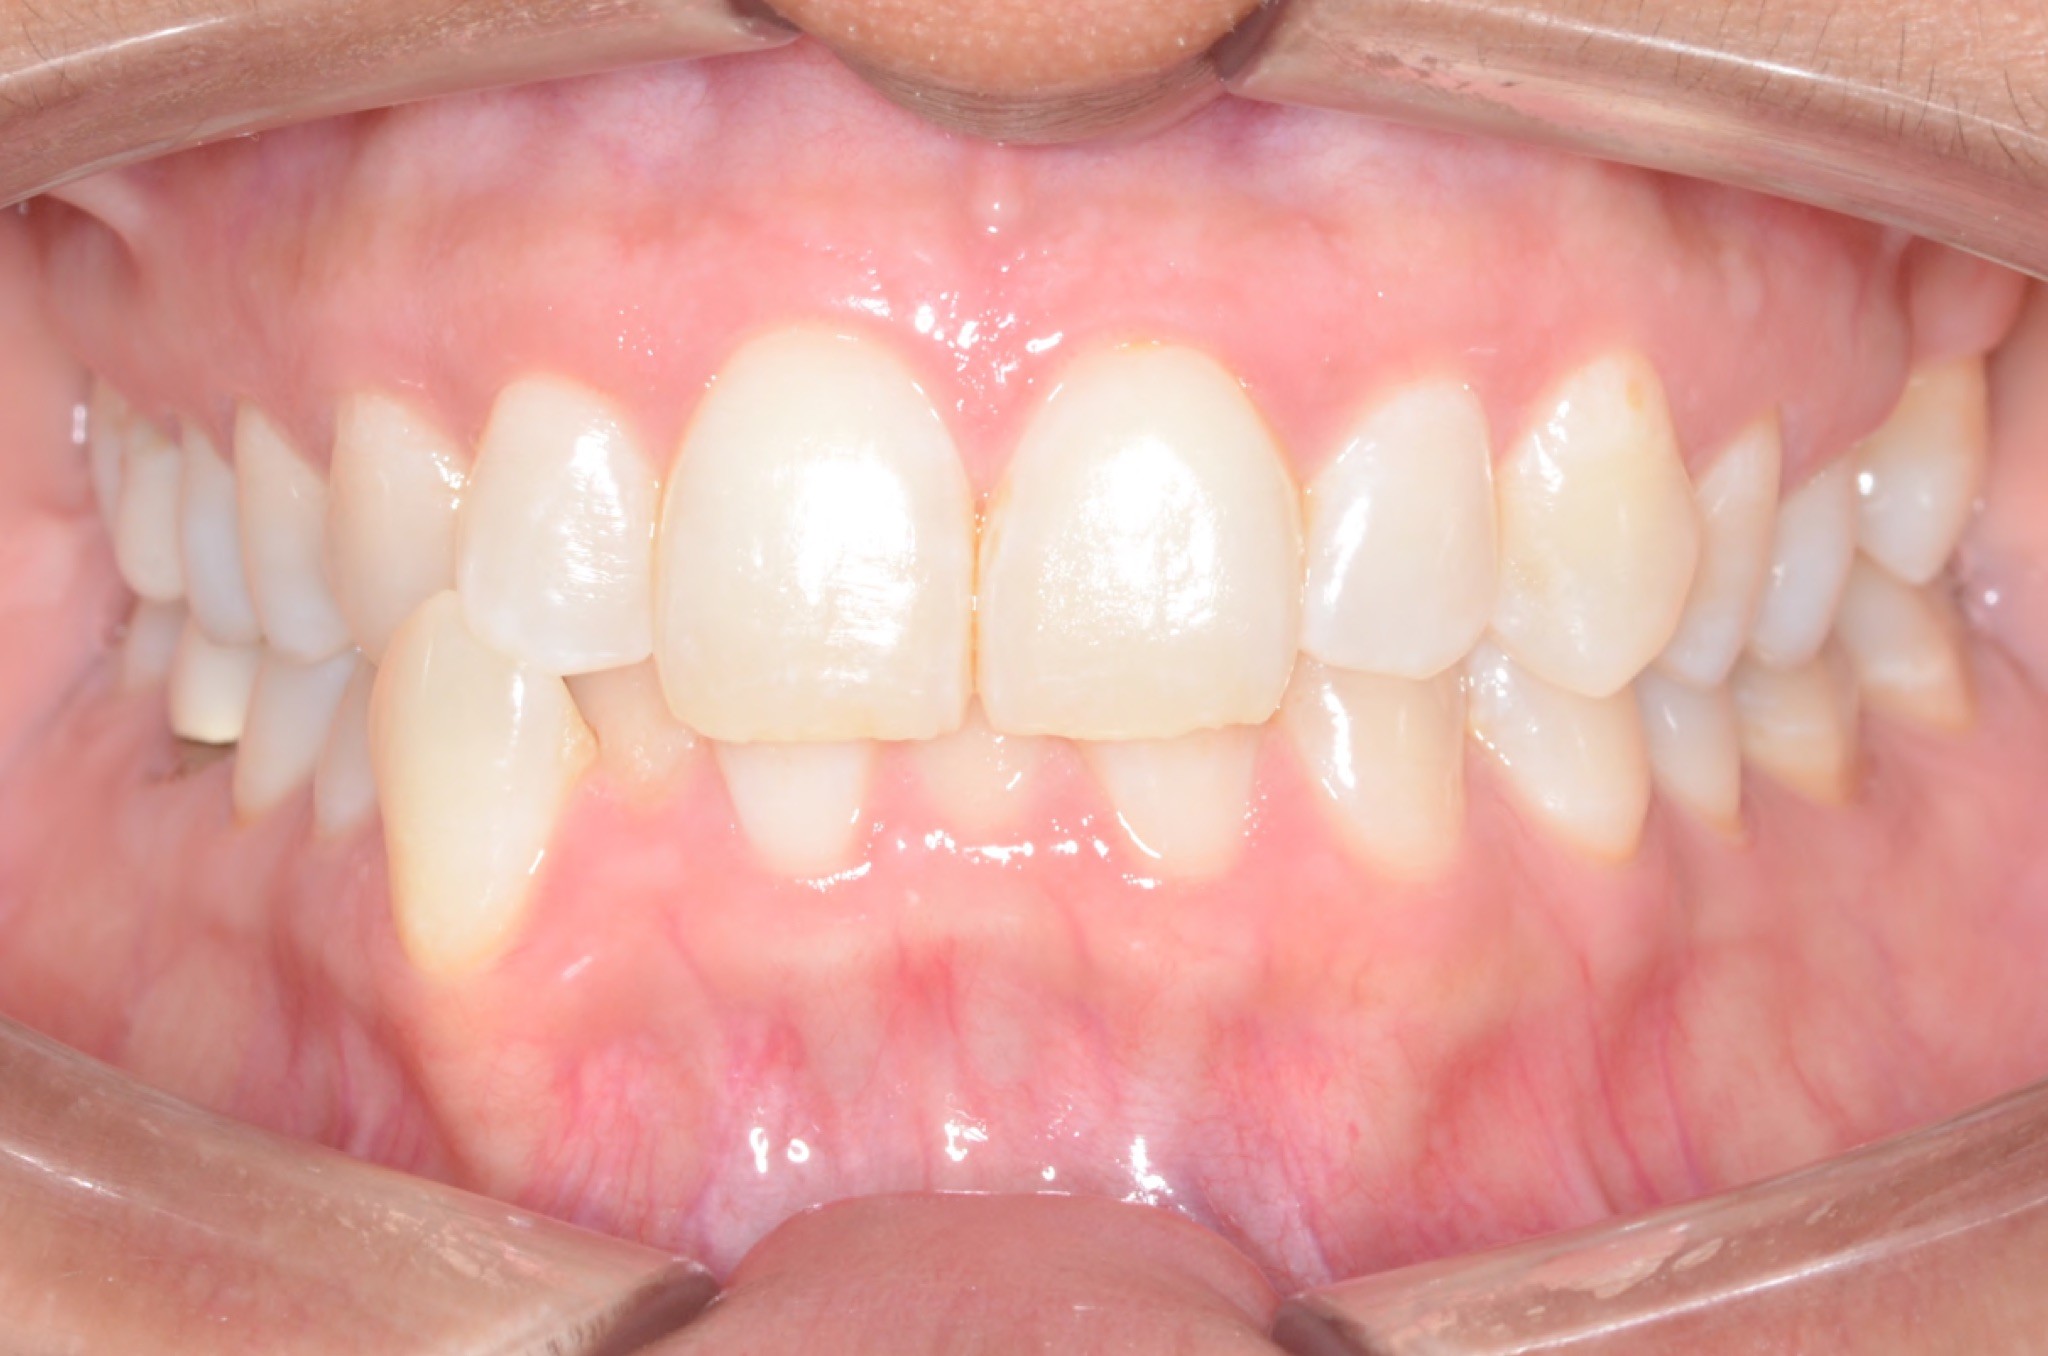

Diagnosis: Lower anterior crowding, LL3 crossbite, deep bite, missing UL6.

Adjuncts: Bite ramps, attachments, IPR

INTRAORAL